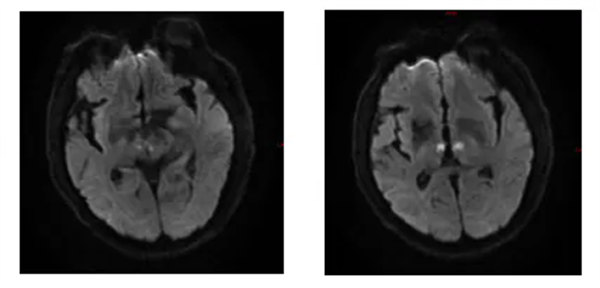

按照過(guò)往的病例來(lái)看,患者已渡過(guò)最危險(xiǎn)的時(shí)刻,只需常規(guī)治療,患者就會(huì)早日康復(fù)出院,然而,出乎所有人預(yù)料,術(shù)后8小時(shí),患者再次出現(xiàn)意識(shí)障礙,雙側(cè)瞳孔光反射減弱呼吸節(jié)律、心律不規(guī)則,病人生命隨時(shí)受到威脅,為什么出現(xiàn)這個(gè)問(wèn)題,問(wèn)題出在哪里?如何解決?還有什么是我們沒(méi)有想到的?患者急性起病,血管再通后癥狀再次出現(xiàn),主要表現(xiàn)為腦干癥狀(意識(shí)障礙、眼球運(yùn)動(dòng)障礙、呼吸心律不規(guī)則)不排除腦干腦炎,在與家屬交待病情并取得家屬同意后立即為患者安排腰穿,然而,腰穿提示:腦脊液常規(guī)未見(jiàn)異常,腦脊液生化蛋白稍高。這一結(jié)果又將診療思路打亂,席聰主任醫(yī)師仔細(xì)查體及詢問(wèn)病史后仍考慮腦血管病,建議再次復(fù)查顱腦DWI,果然,影像提示雙側(cè)丘腦腦梗塞(急性期)。

結(jié)合患者病史、體征、輔助檢查,最終診斷為:雙側(cè)丘腦梗死(Percheron動(dòng)脈梗死)診斷明確,予抗栓、調(diào)脂穩(wěn)定斑塊、清除自由基、改善側(cè)支循環(huán)、針灸康復(fù)等治療,連續(xù)治療3天后患者神志轉(zhuǎn)清、仍有頭暈、垂直注視障礙,至發(fā)病1周后上述癥狀好轉(zhuǎn),遺留輕度垂直注視障礙,出院后繼續(xù)給予腦梗死二級(jí)預(yù)防。

上圖為丘腦旁正中動(dòng)脈的變異:I型指正常解剖;IIa型以源自單一大腦后動(dòng)脈的旁脈為特征。IIb型是指Percheron動(dòng)脈,它是一個(gè)孤立的干,單側(cè)起源于大腦后動(dòng)脈之一,供應(yīng)雙側(cè)丘腦旁正中區(qū)和中腦區(qū);III型的特征是旁脈起源于連接左、右大腦后動(dòng)脈的動(dòng)脈拱廊。該病人為IIb型Percheron動(dòng)脈閉塞,導(dǎo)致雙側(cè)丘腦旁正中區(qū)梗死,病人還出現(xiàn)呼吸、心律不規(guī)則,垂直性注視麻痹癥狀,提示累及中腦。